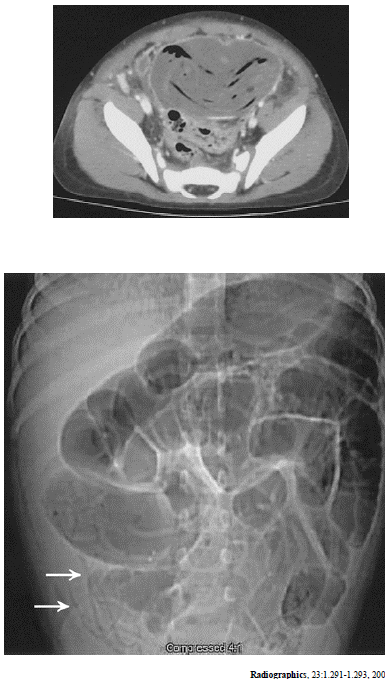

As imagens acima são de um mesmo paciente. Considerando essa imagens e os achados por elas revelados, julgue os itens subseqüentes.

O músculo ilíaco direito apresenta aspecto normal, sem evidências de abscesso.

Existe grande dilatação do cólon sigmóide.

As setas indicam a presença de parasitas.

Há um grande abscesso pélvico.

Há sinais de semioclusão intestinal.

A tomografia foi realizada sem contraste venoso.